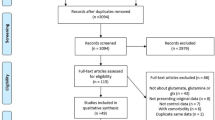

Abstract

Rationale

Lithium is an effective treatment for bipolar disorder, but safety issues complicate its clinical use. The antioxidant drug, ebselen, may be a possible lithium-mimetic based on its ability to inhibit inositol monophosphatase (IMPase), an action which it shares with lithium.

Objectives

Our primary aim was to determine whether ebselen lowered levels of inositol in the human brain. We also assessed the effect of ebselen on other brain neurometabolites, including glutathione, glutamate, glutamine, and glutamate + glutamine (Glx)

Introduction

Six decades after its introduction as a treatment for acute mania, lithium remains the most efficacious treatment for bipolar disorder. As a prophylactic agent, lithium prevents both mania and depression and is the only psychotropic drug shown reliably to decrease suicidal behavior (Miura et al. 2014; Cipriani et al. 2013; Geddes et al. 2010). However, lithium treatment has several drawbacks including poor tolerance, a narrow therapeutic window, longer-term toxicity, particularly for the kidney, and the risk of teratogenicity (McKnight et al. 2012; Shine et al. 2015). Therefore, a form of drug treatment which has the efficacy of lithium without its toxicity would be a worthwhile development.

Rational design of a lithium-like mood stabilizer could be pursued based on its mechanism of action, but lithium’s therapeutic target remains unclear. Based on clinically relevant lithium concentrations (0.6–1.2 mM), the two most likely targets are glycogen synthase kinase 3 and inositol monophosphatase (IMPase) (Berridge et al. 1989; Belmaker et al. 1996; Agam et al. 2009). Recently, we reported inhibition of IMPase by ebselen (IC50 1.5 μM), a bioavailable antioxidant drug that has been tested in humans for other diseases including post-stroke neuroprotection and noise-induced hearing loss (Singh et al. 2013; Lynch and Kil 2009; Azad and Tomar 2014).

We found in animals that ebselen administration lowered brain myo-inositol levels, consistent with functional inhibition of IMPase (Singh et al. 2013), and subsequently in a healthy volunteer study, showed that three 600-mg doses of ebselen over 24 h lowered levels of myo-inositol in the anterior cingulate cortex but not in the occipital cortex as measured by magnetic resonance spectroscopy (MRS) at 3 T (Singh et al. 2015). The aim of the present study was to replicate this finding using a higher dose of ebselen and at a higher field strength (7 T). MRS at 7 T was chosen because the increase in signal to noise ratio (SNR) and spectral resolution allow for more precise metabolite quantification as well as the clear identification of separate glutamate and glutamine resonances as compared to 3 T (Tkáč et al. 2009). Assessment of the effects of ebselen on brain glutamate concentration is of interest because ebselen is reported to inhibit the glutamate-synthesizing enzyme, glutaminase, in vitro (Thomas et al. 2013).